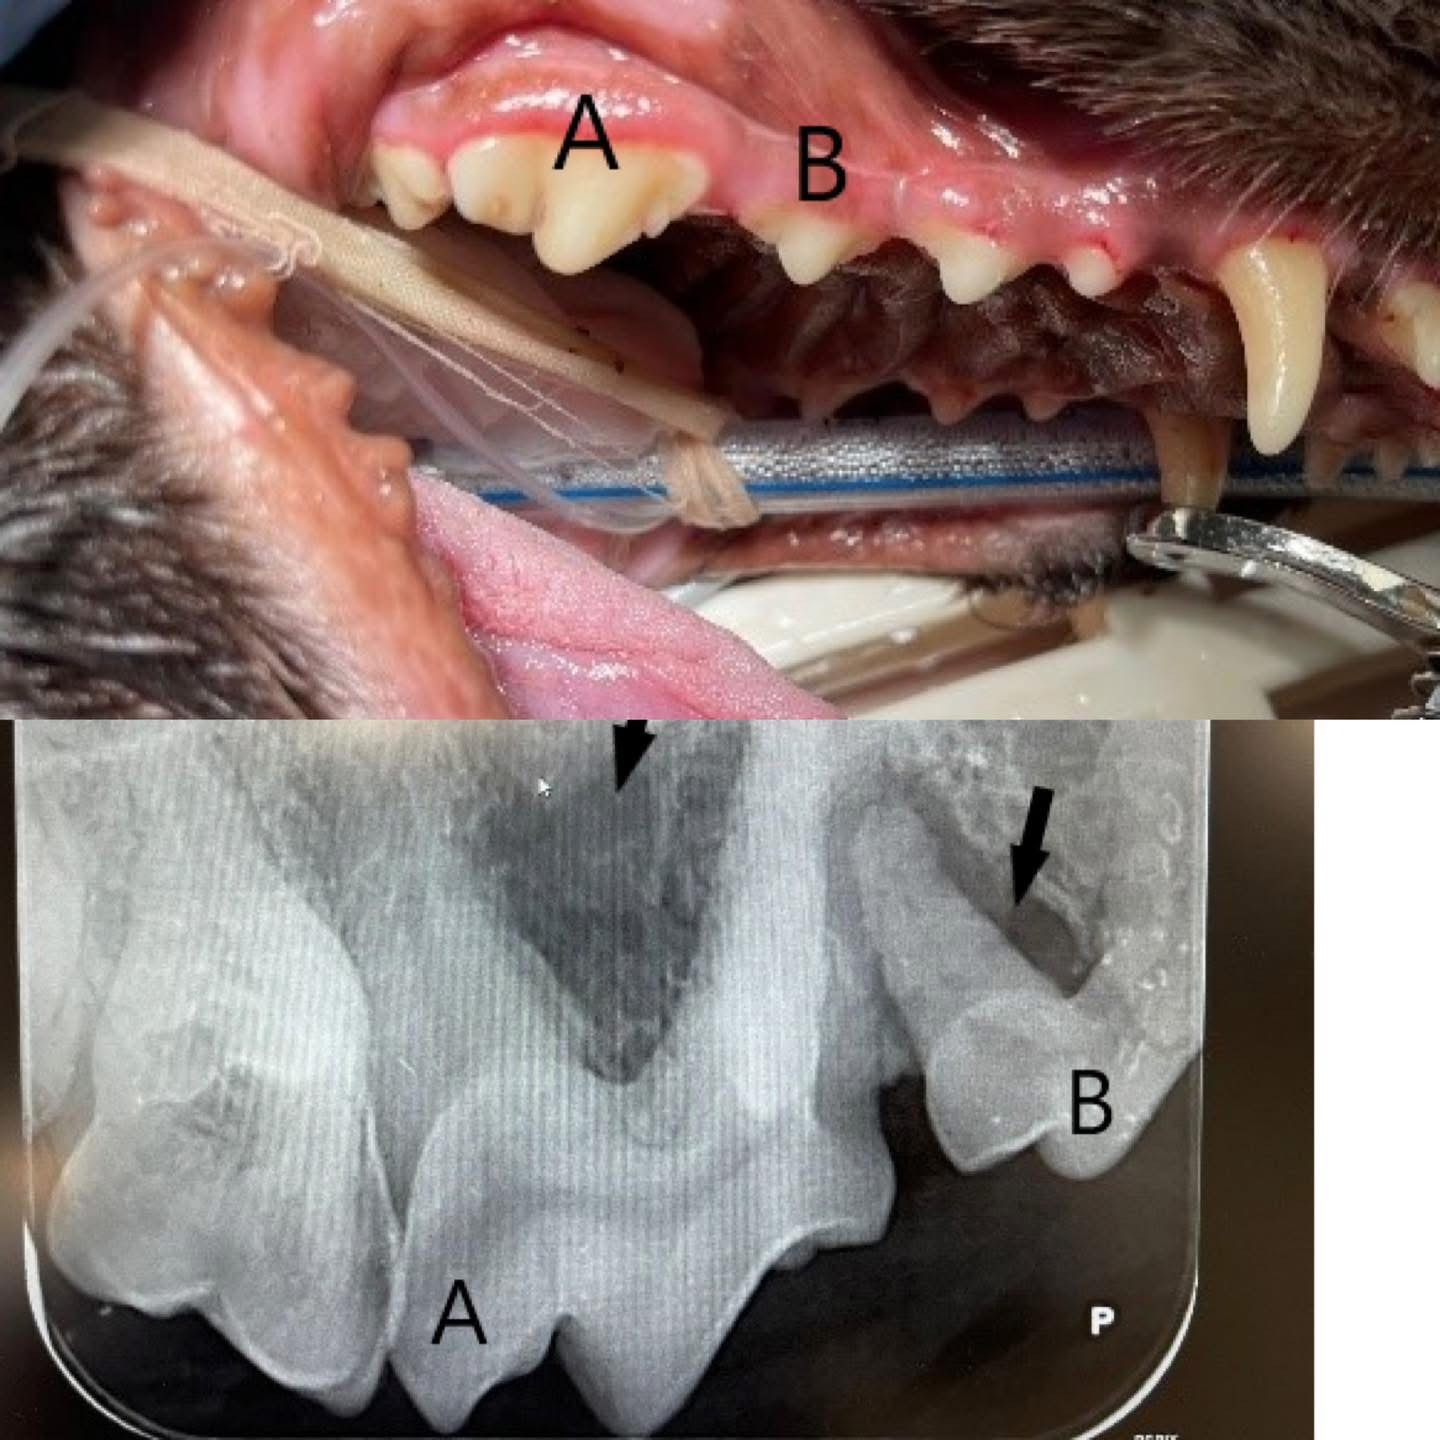

Voorbeeld:

Aan de buitenkant lijkt dit een gezond gebit, röntgenfoto’s laten heel wat anders zien